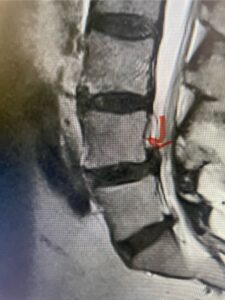

This 54-year-old morbidly obese female presents with progressive back and leg pain and quadriceps weakness. She had no diabetes. She failed all means of conservative management including physical therapy and epidural injections. On imaging she had severe stenosis at L3-4 with a disc protrusion and a slight grade 1 spondylolisthesis at L3-4 (Fig 1). We performed dynamic lumbar x-rays which demonstrated instability at L3-4 and L4-5 (Fig 2). The patient wished to have surgery. We performed an L2-4 decompressive laminectomy and L3-5 in situ fusion because of her instability. Post operatively the patient had relief of leg pain, although the patient was slow to mobilize.

Figs. 1a: Sagittal lumbar T2-weighted MRI demonstrating severe lumbar stenosis with a slight grade 1 at L3-4 and a disc protrusion (red arrow )